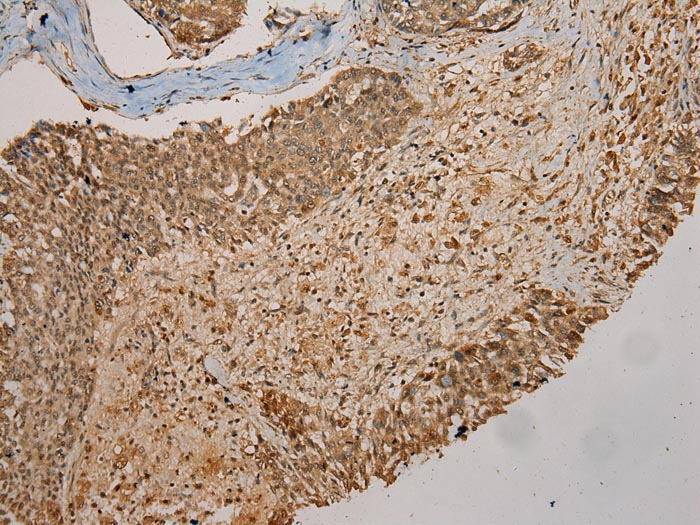

Immunohistochemical analysis of paraffin-embedded Human Liver cancer tissue using #43075 at dilution 1/200.

Immunohistochemical analysis of paraffin-embedded Human Lung cancer tissue using #43075 at dilution 1/200.